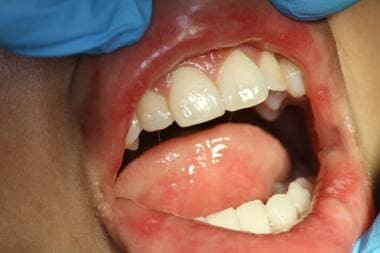

Kenali tanda dan gejala ulkus mulut.

Ulkus mulut adalah luka kecil di area mulut yang bisa muncul di gusi, bibir, bagian dalam rongga mulut, atau langit-langit mulut. Kelainan di rongga mulut ini juga dikenal dengan nama canker sores atau sariawan, merupakan kondisi yang sering dikeluhkan oleh masyarakat pada penyedia layanan kesehatan. Sekitar 20% orang di dunia bisa mengalami ulkus mulut dalam satu waktu semasa hidupnya.

Gejala

Luka di mulut biasanya berwarna putih, kuning atau kelabu di tengah dan dikelilingi tepian berwarna merah. Seseorang bisa memiliki satu atau beberapa ulkus mulut sekaligus. Ulkus mulut bisa disertai dengan pembengkakan di sekitar luka. Ulkus mulut umumnya menimbulkan nyeri, dan keluhan nyeri bisa memberat ketika Anda menyikat gigi, mengonsumsi makanan yang asin, asam atau pedas, minum, atau berbicara.